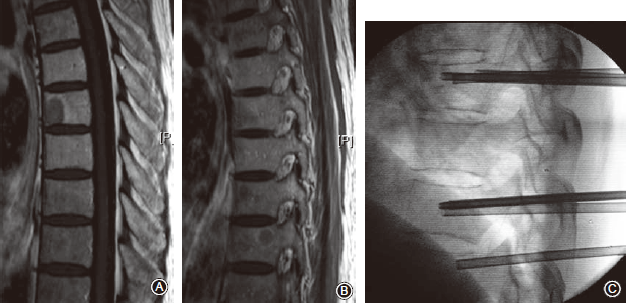

四、影像学评价结果

随访期间影像学复查93.75%(30/32)的患者靶椎控制良好(图3,4);2例(6.25%)患者在术后6个月出现局部病灶进展,临床出现局部疼痛加重并需要止痛药物维持。

此2例分别为乳腺癌和肺癌各1例,肿瘤瘤体直径>2cm且有椎旁软组织肿块等因素与局部进展有关。1例乳腺癌T11转移患者原发肿瘤治疗有效,局部肿瘤进展未引起脊髓压迫症状,该例患者密切随访观察中;另1例肺癌患者局部进展接受外照射治疗。